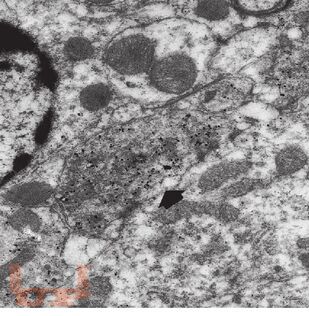

В книге в краткой и доступной форме изложен материал, касающийся достаточно сложных вопросов изучения головного мозга с использованием различных методов иммуногистохимии. В работе представлены сведения о нейральных и глиальных маркерах, применяемых в современных клинических и экспериментальных исследованиях органов нервной системы; приведены результаты ряда нейроморфологических работ, выполненных сотрудниками Института экспериментальной медицины.

Издание адресовано широкому кругу специалистов, использующих иммуногистохимические подходы при оценке состояния органов нервной системы как в патоморфологической диагностике, так и при проведении нейробиологических исследований (неврологам, нейробиологам, физиологам, фармакологам, патологоанатомам, судебно-медицинским экспертам).